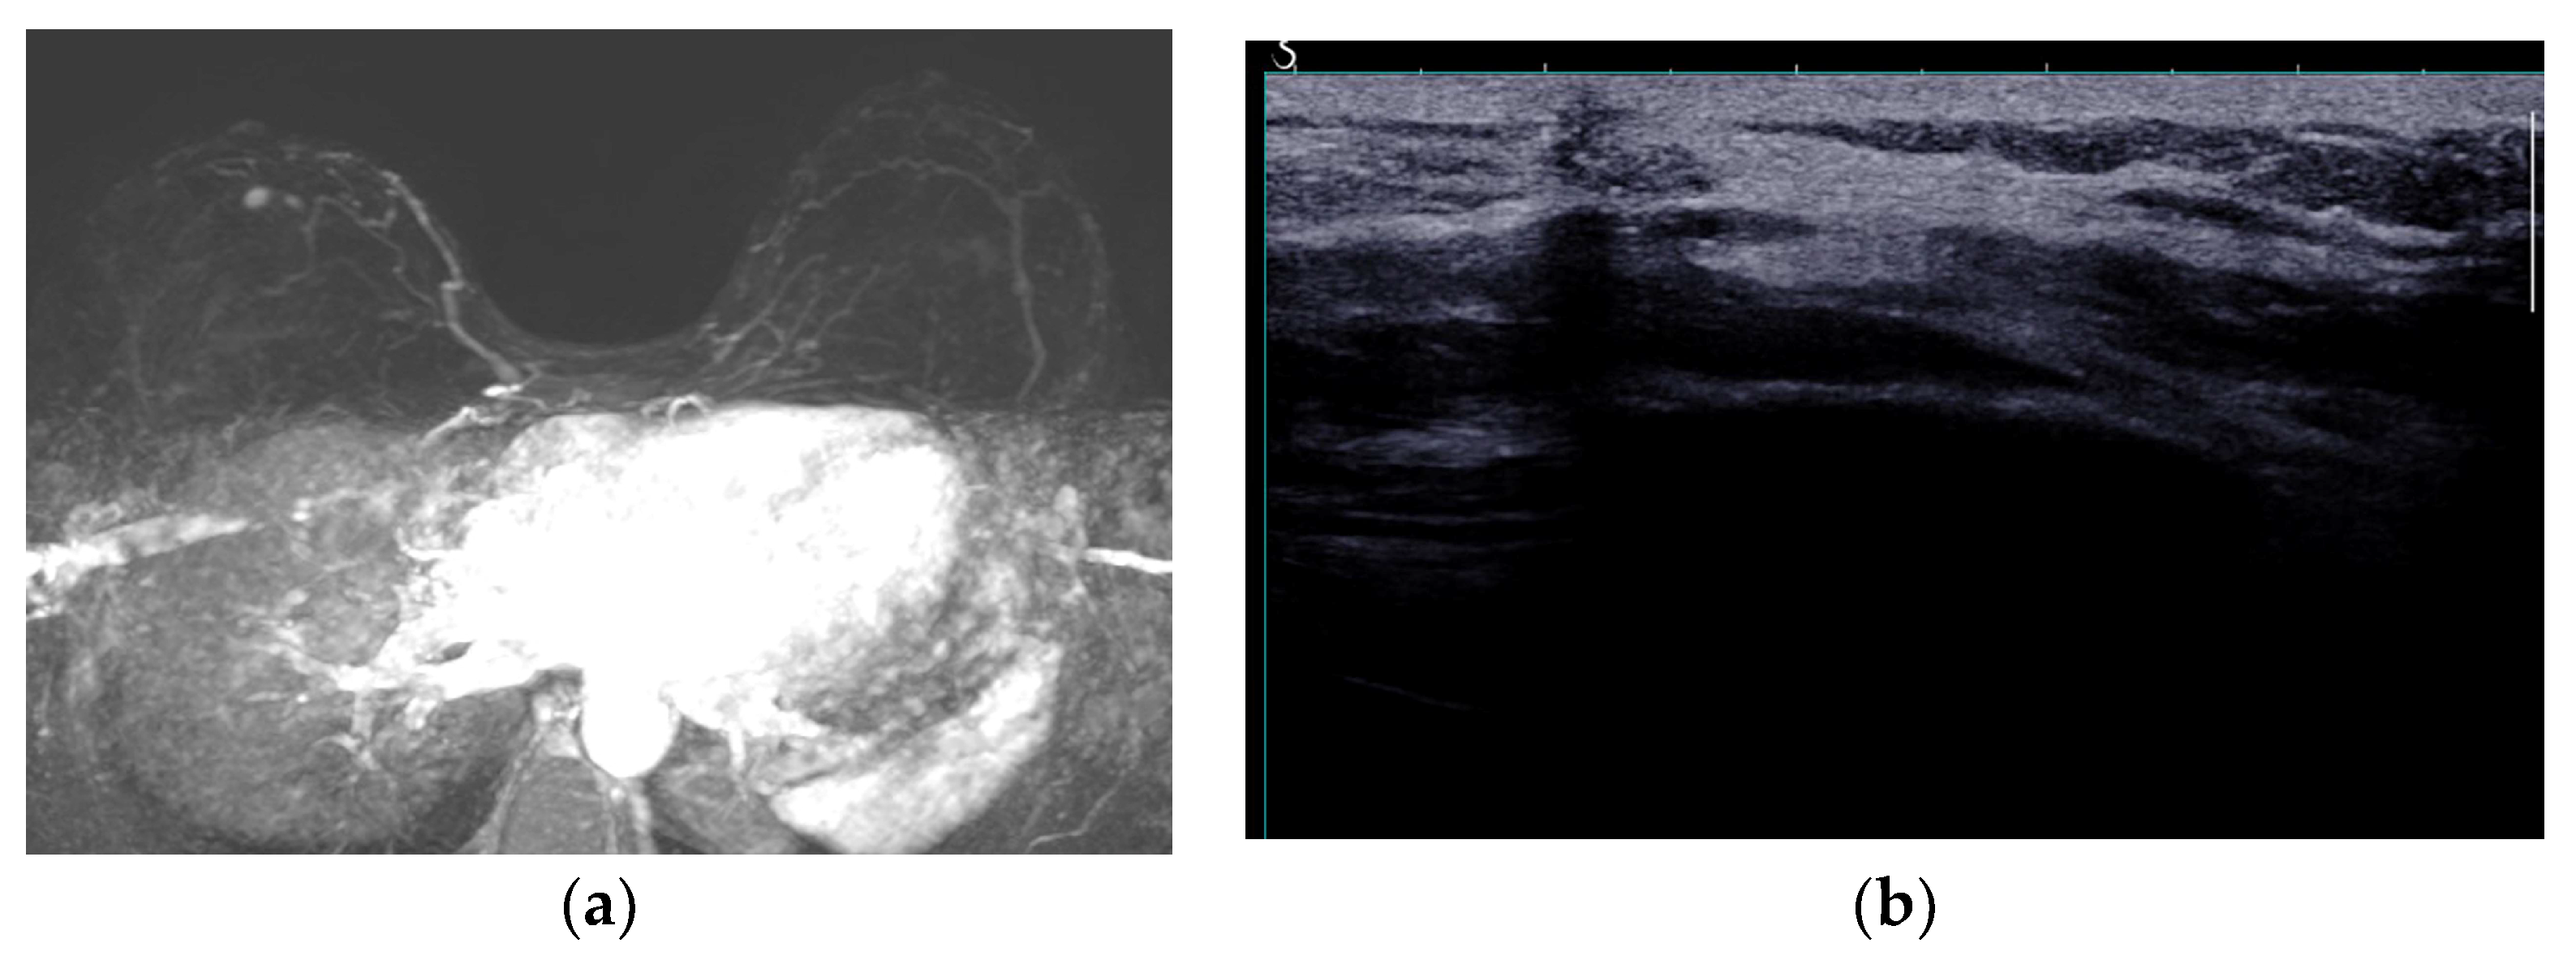

- Sharma, B.; Jurgensen-Rauch, A.; Pace, E.; Attygalle, A.D.; Sharma, R.; Bommier, C.; Wotherspoon, A.C.; Sharma, S.; Iyengar, S.; El-Sharkawi, D. Breast Implant-associated Anaplastic Large Cell Lymphoma: Review and Multiparametric Imaging Paradigms. Radiographics 2020, 40, 609–628. [Google Scholar] [CrossRef] [PubMed]

- Adrada, B.E.; Miranda, R.N.; Rauch, G.M.; Arribas, E.; Kanagal-Shamanna, R.; Clemens, M.W.; Fanale, M.; Haideri, N.; Mustafa, E.; Larrinaga, J.; et al. Breast implant-associated anaplastic large cell lymphoma: Sensitivity, specificity, and findings of imaging studies in 44 patients. Breast Cancer Res. Treat. 2014, 147, 1–14. [Google Scholar] [CrossRef] [PubMed]

- Rotili, A.; Ferrari, F.; Nicosia, L.; Pesapane, F.; Tabanelli, V.; Fiori, S.; Vanazzi, A.; Meneghetti, L.; Abbate, F.; Latronico, A.; et al. MRI features of breast implant-associated anaplastic large cell lymphoma. Br. J. Radiol. 2021, 94, 20210093. [Google Scholar] [CrossRef]

| Complications | Fluid | Early; low T1, high T2 | Seroma |

| Delayed, persistent (±mass) | BIA-ALCL, BIA-SCC | ||